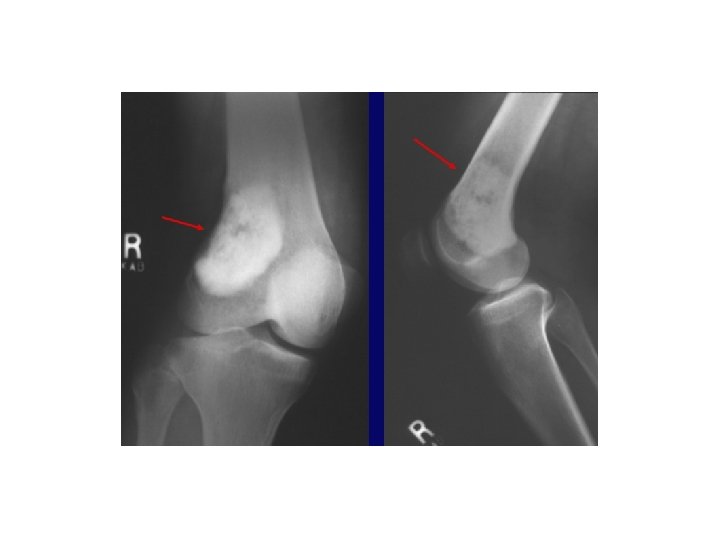

DISLOCATION

DISLOCATION • Note the dislocation on the previous slide; the articular surfaces of the knee no longer maintain their normal relationship • Dislocations are named by the positioin of the distal segemnt • This is an Anterior knee dislocation